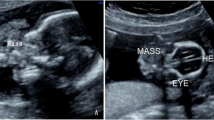

A male newborn (a son of a 19-year old primiparous healthy mother—delivery was by cesarean section in the 33rd week of gestation, family history of multiple births was not remarkable) was admitted to the Intensive Care Department of the University Children’s Hospital in Kraków in the first day of life due to a large intracranial tumor. The tumor was diagnosed in the 31st week of gestation during routine ultrasound examination and confirmed by MRI (Fig. 1a, b). The pregnancy was terminated in the 33rd week of gestation with prior induction of lung maturation by dexamethasone administered to mother.

a MRI SSFSET2, sagittal plane. A solid, cystic expansive process, arising from the temporal region and growing extra and intracranially in the head of the fetus, is seen (asterisk). The brain of the fetus is marked with an arrowhead. b MRI T2, an axial view of the head of the fetus. A marked discontinuity of the cranium and tumoral mass is visible. c CT of the head of newborn. A tumor is expanding within the structures of the craniofacial region of the head